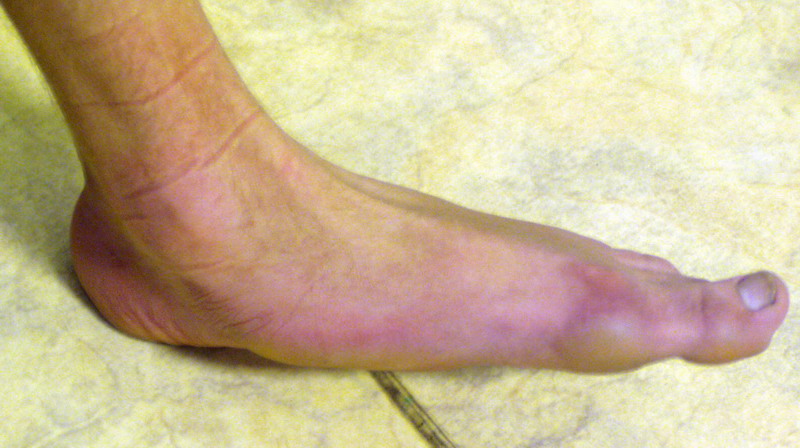

Пациент 15 л., болезнь Литтля, спастический нижний парапарез, интеллект высокий. Ребенок настроен на активный образ жизни. С недавнего времени начал ходить без дополнительной опоры. Появилась проблема с левой стопой - во время ходьбы опора приходится на смещенную кнутри таранную кость.

Может образоваться болезненный натоптыш или язва.Общепринятой операцией является трехсуставной артроде с мобилизацией таранной кости. Выполнять такую операцию у спастика и в раннем возрасте проблематично. Родстьвенники тем более готовы материально и морально осуществить хирургическое лечение за рубежом, если оно показано и возможно.Предпочтительно в Австрии и Германии. Если кто-то посоветует координаты таких клиник - были бы признательны.